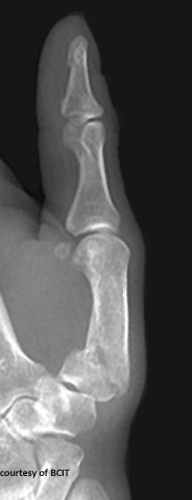

What is a Bennett’s fracture and how does it happen?

An oblique intra-articular fracture at the base of the 1st metacarpal with subluxation, caused by axial load, hyperabduction, or hyperextension of the thumb.

What is the treatment for Bennett's fracture and why is it significant?

Fixation with pins or K-wires; loss of thumb function (opposition/grip) is a serious concern.